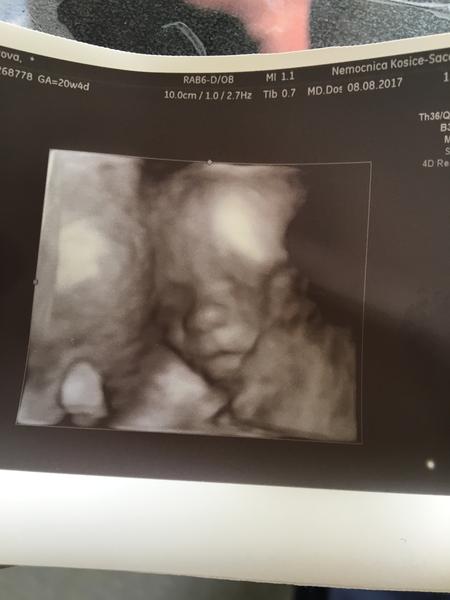

@karmela ešte neviem možno sa zajtra dozvieme idem na prvotrimestralny skríning tak hádam sa ukáže. Dnes mi ho gynda ukázala aj na 3D ale nechcelo sa fotiť 😂 ručičkami si zakryvalo tváričku 😍 a ti poviem nehybne ho pristihnúť to bolo ťažké tak sa mrvilo a skackalo sinv brušku občas ho musela fajne štuchnut aby sa otočilo ako chcela 😊 no neposedné mimčo. Uvidíme zajtra či sa ukáže drobček. Vieš čo keď som tak dnes naňho pozerala no úplne sa mi zdalo že bude mať môj Orli nos 😁 tak som si v duchu pomyslela aha môj Orli nos má 😁 bolo to krásne 😍 2.11 mám ďalšiu poradňu dúfam že to už bude ísť rýchlejšie lebo hrozne pomalu mi to ide zatiaľ.